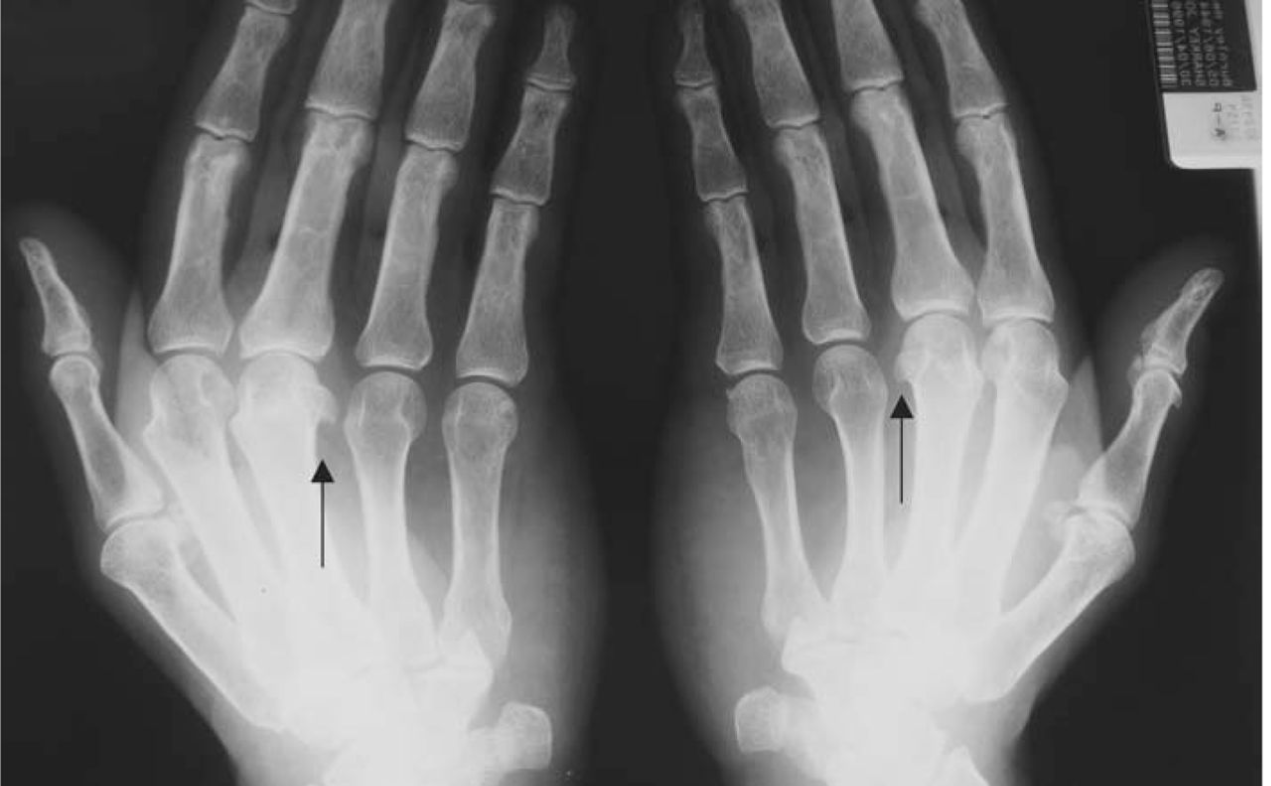

55 Yo M notes pain in his hands and swelling in his fingers, it is hard to flex his fingers now. has a history of long standing low back pain

Q: What is his diagnosis?

Psoriatic Arthritis

Pencil & Cup, dactylitis

joints: wrist, MCP, PIP, DIP

50 Yo M prior professional football player presents with bilateral pain in his hands. Notes minimal pain in the morning, worse when using his hands a lot. A doctor placed him on MTX in the past without benefit.

Exam: tender MCP joints

This patient has hemochromatosis, order ferritin